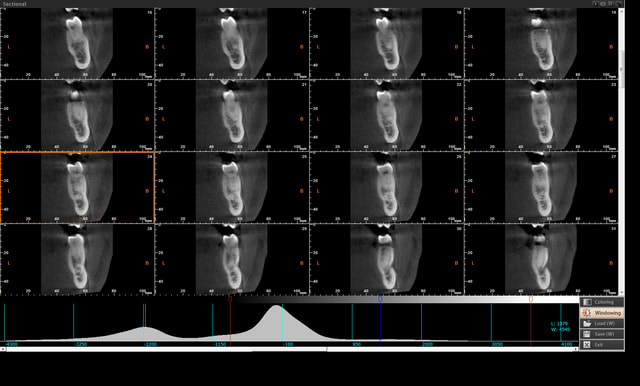

exemple de coupe mandibulaire pour visualiser le nerf dentaire

renommer le .txt en .avi pour avoir un film de toute les coupes...